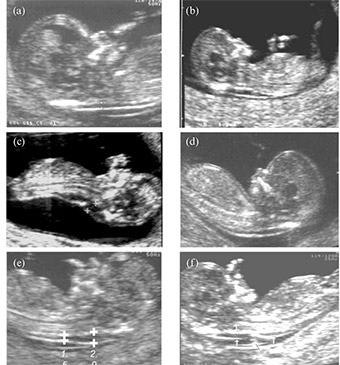

U periodu od 11. do 14. GN procenjuje se rizik od hromozomopatija. U predelu iza vrata bebe pojavljuje se nakupina fluida – nuhalna translucenca (NT). Pojava hromozomskih anomalija povezana je sa dimenzijom ove strukture.

U ovom periodu pregleda se anatomija ploda koja sadrži: kranijum, moždane strukture, nosnu kost, srčanu radnja, želudac, inserciju pupčanika, ruke, noge, protok kroz duktus venosus.